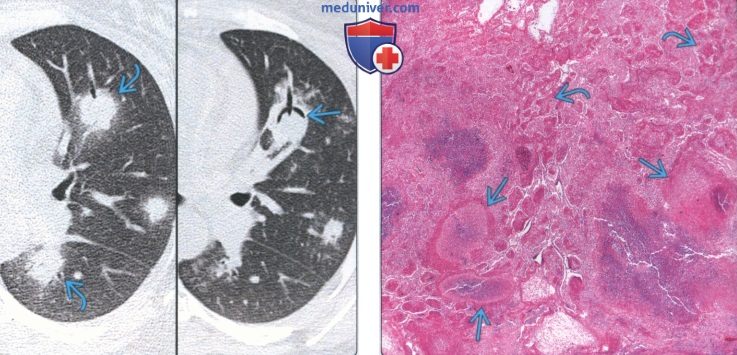

Визуализация и диагностика неинвазивного аспергиллеза с помощью КТ

Раздел: Необычные решения